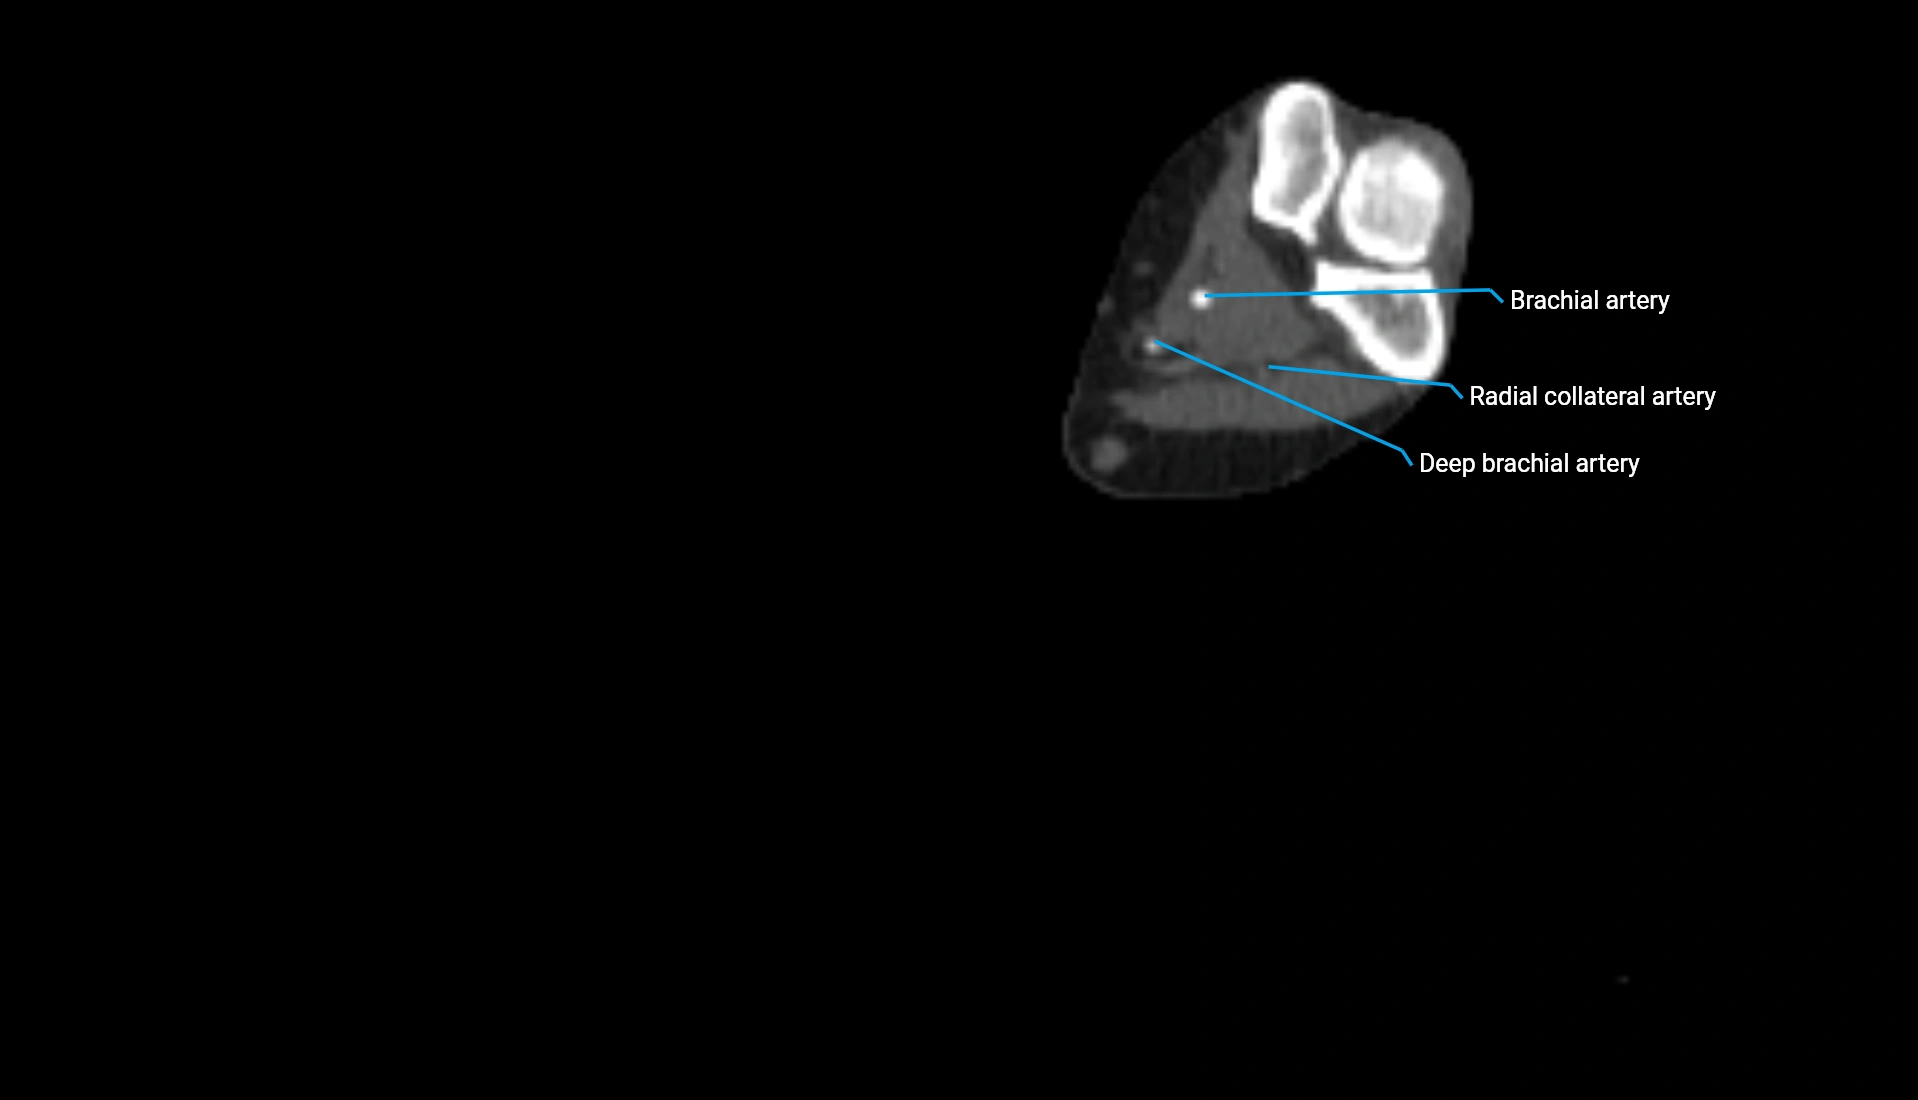

CT Appearance

Non-Contrast CT:

• Cortex: High-density, sharply defined

• Subchondral bone: Dense cancellous matrix

• Articular surface: Smooth concave contour articulating with the capitellum

• Excellent for evaluating bone integrity, alignment, and subtle fractures